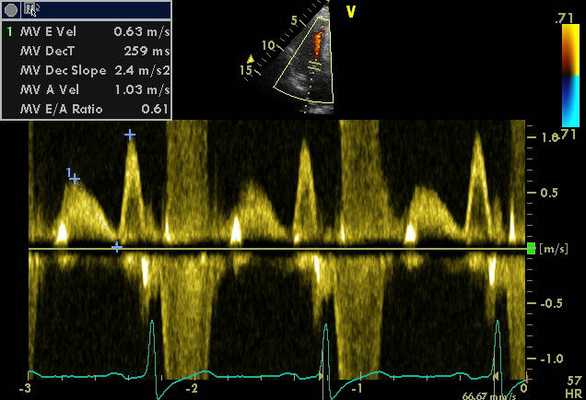

- Измерение скоростей входящего митрального потока, времени его замедления, параметров кровотока в легочных венах и тканевая допплерография в области кольца митрального клапана позволяет достаточно точно оценить диастолическую функцию ЛЖ, включая давление наполнения ЛЖ.